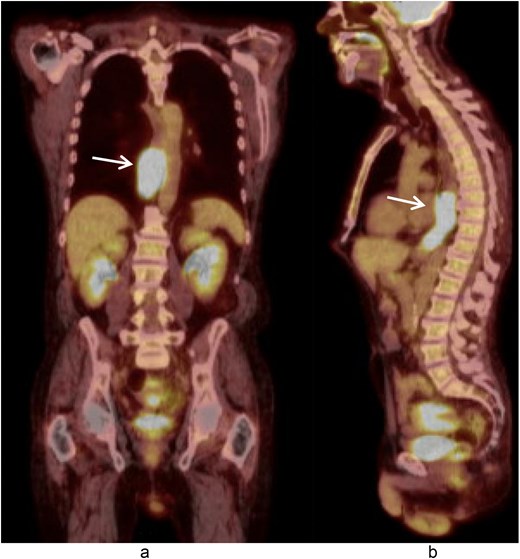

A 58-year-old male with a history of hypertension, daily alcohol use, and 35 pack year smoking history presented with progressive dysphagia and significant weight loss over a period of 3 months. His symptoms began with heartburn, with initial failure of empiric treatment for reflux. He then developed dysphagia to solids that progressed to liquids and eventually an inability to tolerate his own saliva. Over that timeframe, he also noted unintentional weight loss of ~30 lbs. He eventually presented to the emergency department where a CT scan raised concern for an obstructing esophageal mass (Fig. 1). He urgently underwent upper endoscopy revealing a large polypoid tumor with a broad base located in the lower esophagus (Fig. 2). Biopsies revealed a high-grade malignant neoplasm with spindle cell features concerning for a sarcoma. Further workup with brain MRI and positron emission tomography (PET) scan confirmed a hypermetabolic esophageal mass without evidence of distant metastatic disease (Fig. 3). Unfortunately, endoscopic ultrasound was unable to be performed given the nearly obstructive nature of the tumor.

Coronal (a) and sagittal (b) views of the PET scan showing area of hypermetabolic activity at the lower esophagus without evidence of distant disease (arrows).